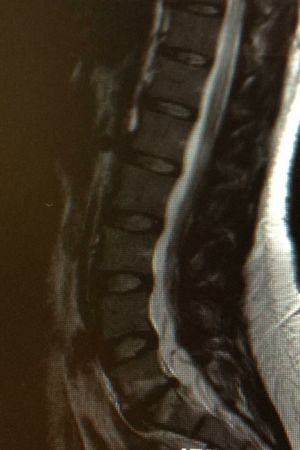

What is this???

Spine

Tethered spinal cord and syringomelia.